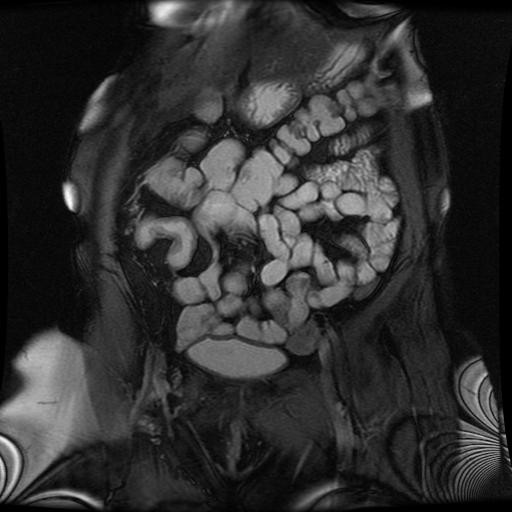

Pracownia Rezonansu Magnetycznego

Pracownia wykonuje badania MR dla oddziałów SU w Krakowie oraz dla pacjentów ambulatoryjnych ze skierowaniem w ramach NFZ. Wykonuje również badania w ramach projektów naukowych i badań klinicznych.

Pracownia MR została uruchomiona w roku 1998 jako pierwsza w regionie Polski Południowo-Wschodniej. Mieści się obecnie w budynku CUMRiK (ul. Kopernika 50). Pracownia dysponuje wysokiej klasy systemem do rezonansu magnetycznego o natężeniu pola 1,5 T. Umożliwia on obrazowanie, a także wykonywanie szeregu bardzo zaawansowanych badań MR. Opracowywanie wyników umożliwiają diagnostyczne stacje komputerowe, na których pracują lekarze specjaliści radiolodzy i fizycy medyczni.

Aparat jest bogato wyposażony (dedykowane cewki, automatyczna strzykawka przystosowana do pracy w polu magnetycznym, automatyczny przesuw stołu), a także oprogramowany, co pozwala na wykonywanie, oprócz podstawowych, także szeregu badań specjalistycznych:

ˇ badanie perfuzyjne mózgu (z i bez środka kontrastowego)

Diagnostyczne stacje komputerowe pozwalają na przekształcanie danych obrazowych oraz otrzymywanych w badaniach spektroskopowych i czynnościowych. Oprócz klasycznych przekrojów można otrzymać obrazy trójwymiarowe oraz w opcji wirtualnej endoskopii naczyń, dróg żółciowych i moczowych czy układu komorowego mózgu.